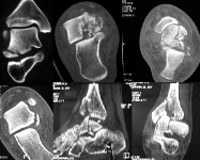

CT of the foot.

Показаниями к КТ стопы являются травмы, сопровождающиеся сильной болью при осевой нагрузке, движении или покое, отечность, гематома, патологическая подвижность или потрескивание костей; подозрение на проникновение инородных тел с отрицательным рентгеновским излучением; деформация стопы и голеностопного сустава; появление рака с неопределенной этиологией. Заболевания, которые могут потребовать диагностики, включают деформацию остеоартрита, подагру, ревматоидный артрит, остеомиелит, хронические и рецидивирующие вывихи и отрицательные рентгенологические переломы. В меньшей степени этот тест используется для диагностики повреждения связок и сухожилий.